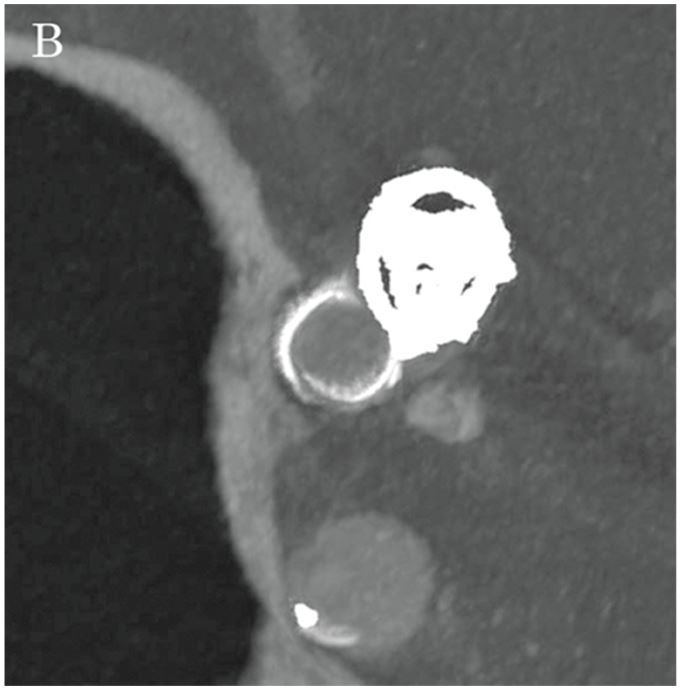

Флюорографічні зображення, отримані за допомогою Hi-Def Detector, дозволили чітко спостерігати поведінку котушки та мікрокатетера, а також розгортання стенту за допомогою високороздільних зображень, що забезпечило надзвичайно ефективну підтримку під час процедури (малюнки 2A та 2B). Далі, за допомогою опції Alpha CT (конусно-променевої комп'ютерної томографії), було підтверджено стан розгортання стенту та затискування головної судини (малюнки 3А та 3В), після чого проведено додаткову емболізацію з використанням спіральних котушок в зоні втікання до аневризми. Лікування було завершено із щільністю запаковування котушкою у 28,24%. Наявність або відсутність інтранкраніального крововиливу було підтверджено за допомогою Alpha CT.

Малюнок 2B: DA (натив) під час від’єднання Axium PRIME (5 × 10 мм).

Малюнок 3B: Alpha CT мультипланарна реконструкція, що показує зображення середньої точки стента LVIS по короткій осі.